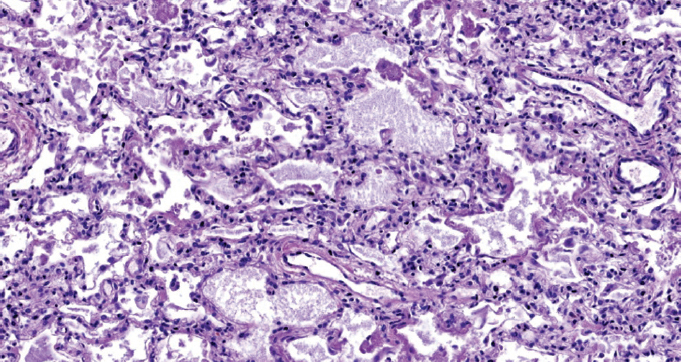

Children get sick less often than adults with a new coronavirus infection (in the Russian Federation, they account for 7.6% of registered cases of COVID-19), with less severe clinical symptoms, they require hospitalization less often, their disease is milder. The frequency of severe and extremely severe cases of COVID-19 in children does not exceed 1%. A clinical case of the course of COVID-19 in a child aged 2 years 4 months is presented. with acute lymphoblastic leukemia. A feature of the presented case is the development of an extremely severe new coronavirus infection in a child with secondary immunodeficiency caused by a long-term course of malignant, treatment-resistant of acute lymphoblastic leukemia. Slow, within 3 months, the development of the infectious process with long-term preservation of normal indicators of the function of the respiratory system led to the formation of viral-bacterial pneumonia with the development of respiratory distress syndrome. Despite the modern complex of therapeutic measures, severe comorbidity led to the development of DIC and multiple organ failure, which was the direct cause of the child’s death. A possible therapy strategy is discussed in a patient with severe comorbidity against the background of secondary immunodeficiency and long-term persistence of SARS-CoV-2 in the presence of IgG antibodies to SARS-CoV-2 in the blood. For the first time, data on morphological changes in the lungs with a long course of COVID-19 (more than 100 days) in a young child are presented.